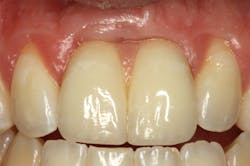

Loss of interdental papilla after extraction can be compensated for with pink porcelain when adjacent implants are splinted. Also, splinting can simplify clinical procedures and enhance esthetics (figure 4).

Figure 4: Esthetic considerations